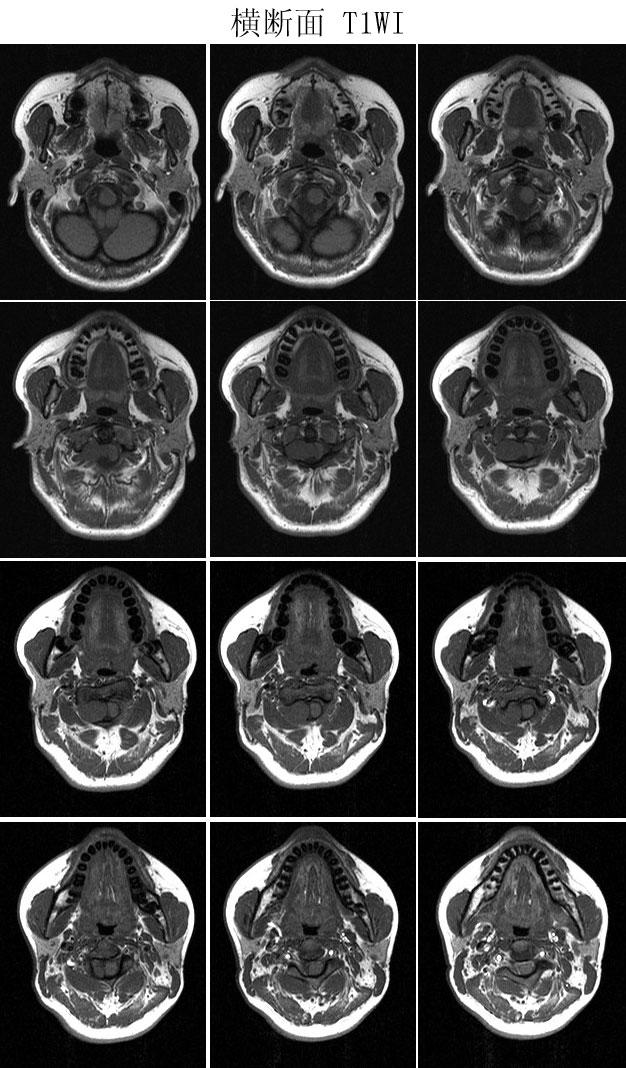

本病例来自广东同江医院

病史:女,27岁,洗头按摩时扭颈导致昏迷,检查发现颈椎占位

手术病理:

神经鞘瘤